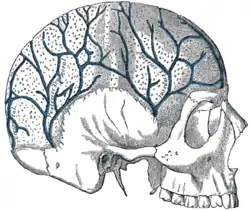

Veins of the diploë as displayed by the removal of the outer table of the skull. | |

Diploë (/ˈdɪploʊi/ or DIP-lo-ee) is the spongy cancellous bone separating the inner and outer layers of the cortical bone of the skull.[1] It is a subclass of trabecular bone.[2]

In the cranial bones, the layers of compact cortical tissue are familiarly known as the tables of the skull; the outer one is thick and tough; the inner is thin, dense, and brittle, and hence is termed the vitreous table. The intervening cancellous tissue is called the diploë. In certain regions of the skull, this becomes absorbed so as to leave spaces filled with liquid between the two tables.